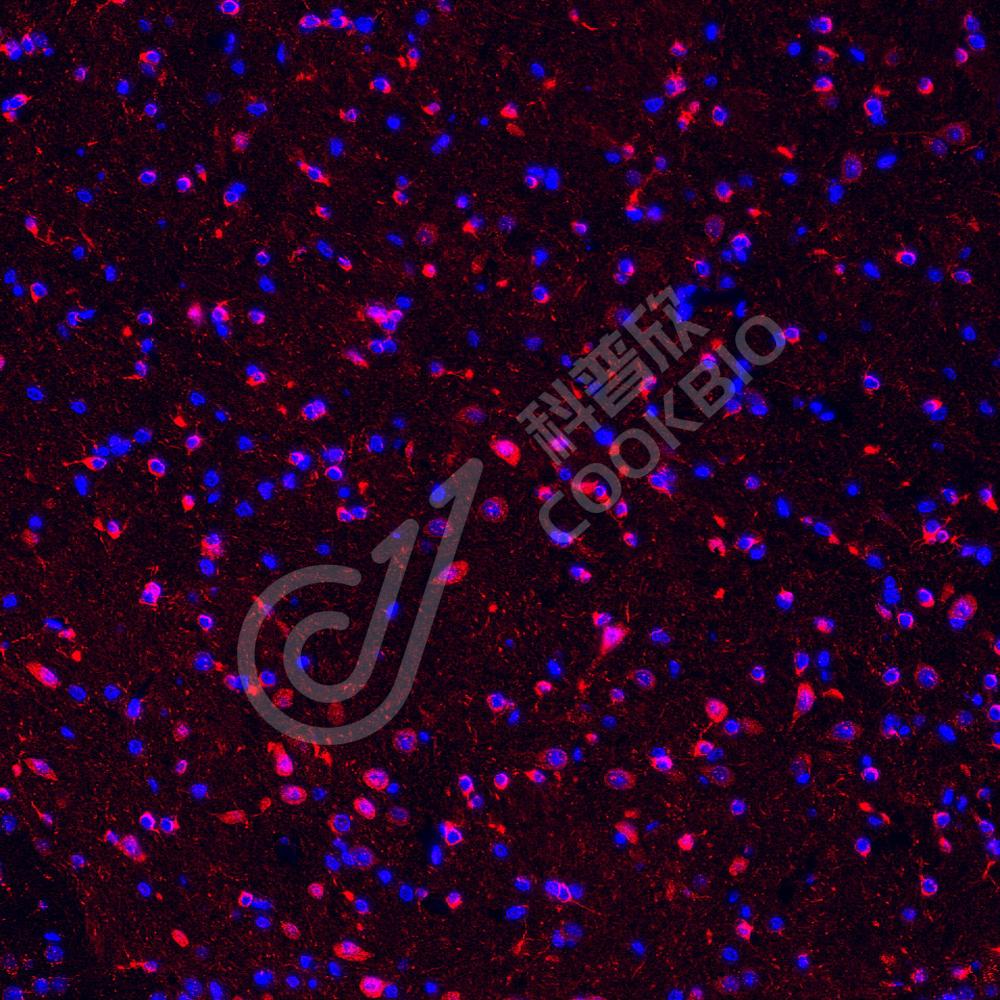

IHC/IF 免疫组织化学/免疫荧光

物种:小鼠,大鼠

稀释比:1:500-1:2000

阳性样品:肺

IHC检测HSPA6蛋白(货号 K1334980).

样品: 小鼠肺, 4%多聚甲醛 (货号KSG1101) 固定12-24小时.

抗原修复: 柠檬酸抗原修复液(干粉, pH 6.0) (KSG1201), 98℃, 20分钟.

—抗: 1: 1300稀释, 4℃ 孵育过夜.

二抗: S-vision免疫组化多聚二抗(山羊抗兔),即用型 (货号KB3906), 室温孵育20分钟.